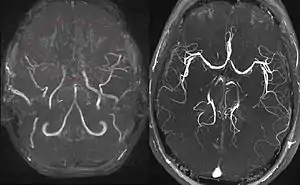

Right: healthy patient, for comparison.

Cerebral angiography is the gold standard of diagnosing moyamoya disease and its progression. According to Suzuki's system, it can be classified into six stages:[14]

Magnetic resonance angiography (MRA) is also useful in diagnosing the disease with good correlation with Suzuki's grading system.[14]